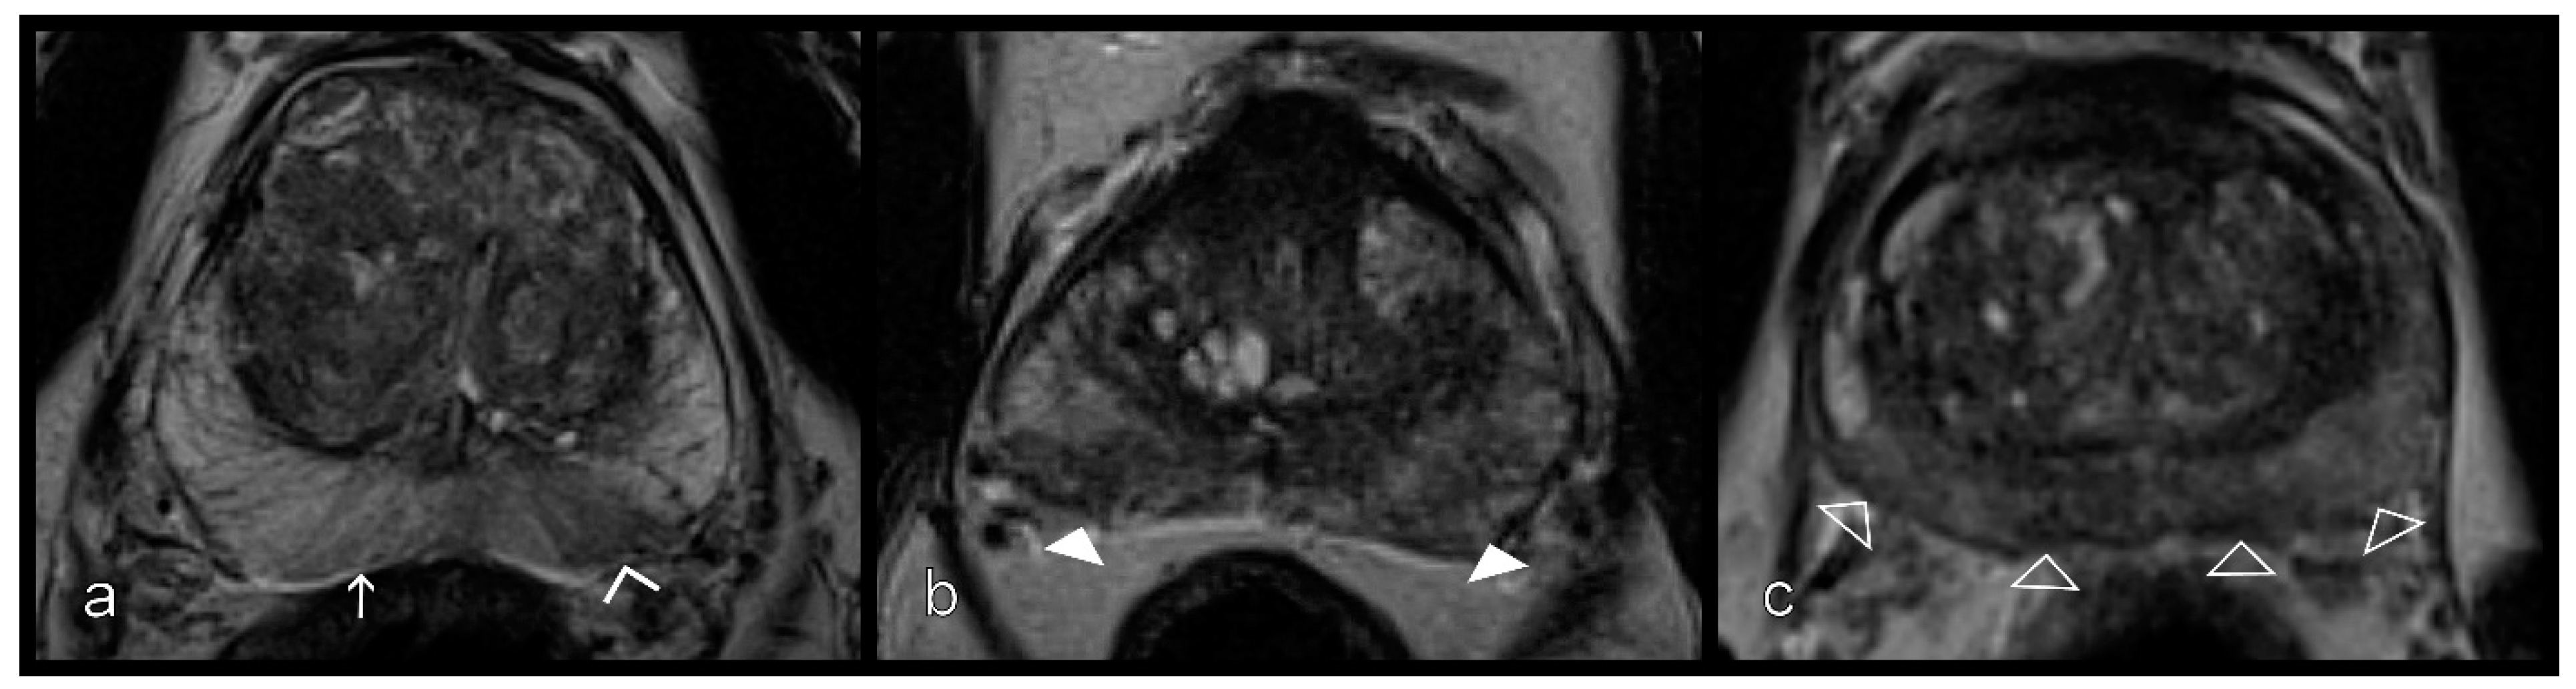

Figure 3.

Inflammatory changes in the peripheral zone from left to right. (a) Stripes (white arrow) and sharp wedges (empty arrowheads), (b) wedges with obscured margins (white arrowheads), and (c) patchy and diffuse signal reduction (empty arrowheads) on T2W sequences.